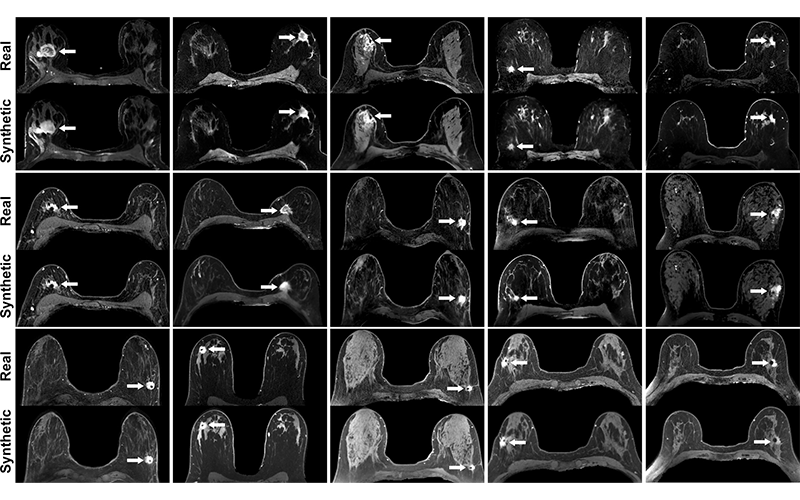

Real versus simulated (ie, synthetic) contrast-enhanced T1-weighted axial breast MRI scans of patients with invasive breast cancer. Pairs of real and simulated contrast-enhanced breast MRI scans from 15 patients with invasive breast cancer (arrows). Intrathoracic and extramammary structures were masked in all images. https://doi.org/10.1148/radiol.213199 ©RSNA 2022

For qualitative assessment, four breast radiologists, blinded to whether the method of contrast was real or simulated, assessed image quality, presence of tumor enhancement, and maximum index mass size by using 22 pairs of real and simulated contrast-enhanced MRI scans.

The readers assessed all simulated scans as having the appearance of a real MRI scan with tumor enhancement, while index mass sizes on real and simulated scans demonstrated good to excellent agreement. Readers rated 95% of the simulated MRI scans to be of diagnostic quality.